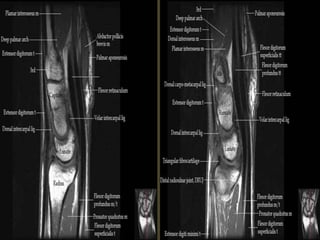

Wrist X-ray Anatomy.